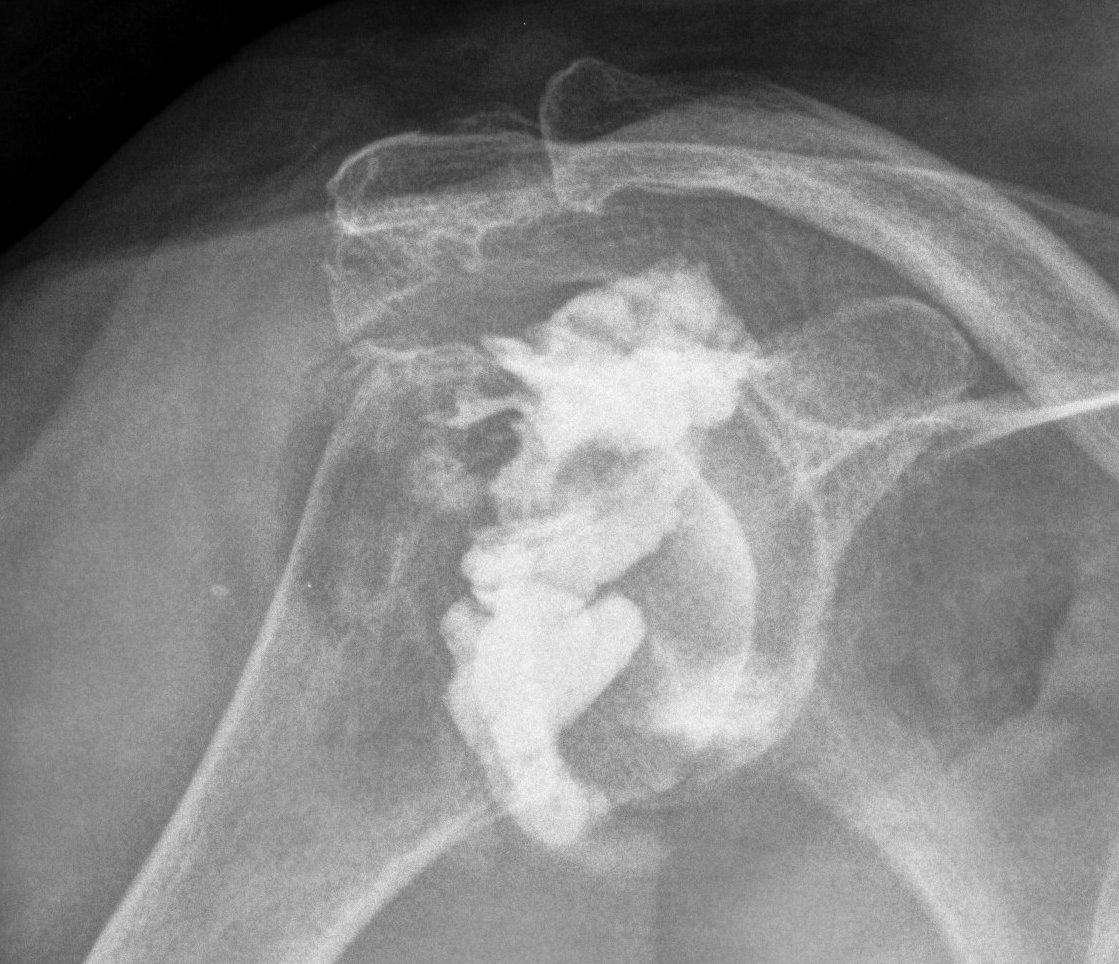

Destructive RA

Glenoid deficiency

Levigne and Franceschi Classification

Three main patterns